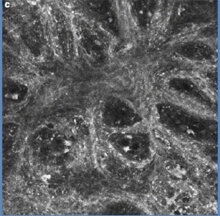

Examen en microscopie confocale ou biopsie virtuelle :

La microscopie confocale (confocal laser scanning reflectance microscopy) est un examen fait dans quelques centres spécialisés. Elle permet d’obtenir sur le vivant des images microscopiques de la peau en coupes autrefois seulement envisageable qu’après ablation chirurgicale de la lésion. En dehors de sa rareté, de son coût et de la formation hautement spécialisée nécessaire – la profondeur de l’examen est limitée à 0,3 mm sous la peau. Cet examen permet parfois d’éviter une biopsie inutile quand l’examen à l’oeil nu et au dermatoscope ne permettent pas de certitude. Cet examen est utile dans les localisations délicates ou une biopsie laisserait une marque – seins, organes génitaux, visage…

![]() |

|

Microscope confoncal Vivascope® et mélanome en microscopie confocale